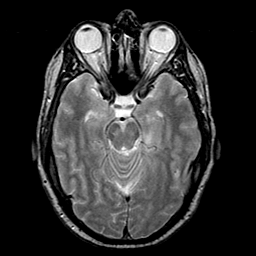

glioma overlay -- Slice #10

[Home][Help][Clinical] Slice 10